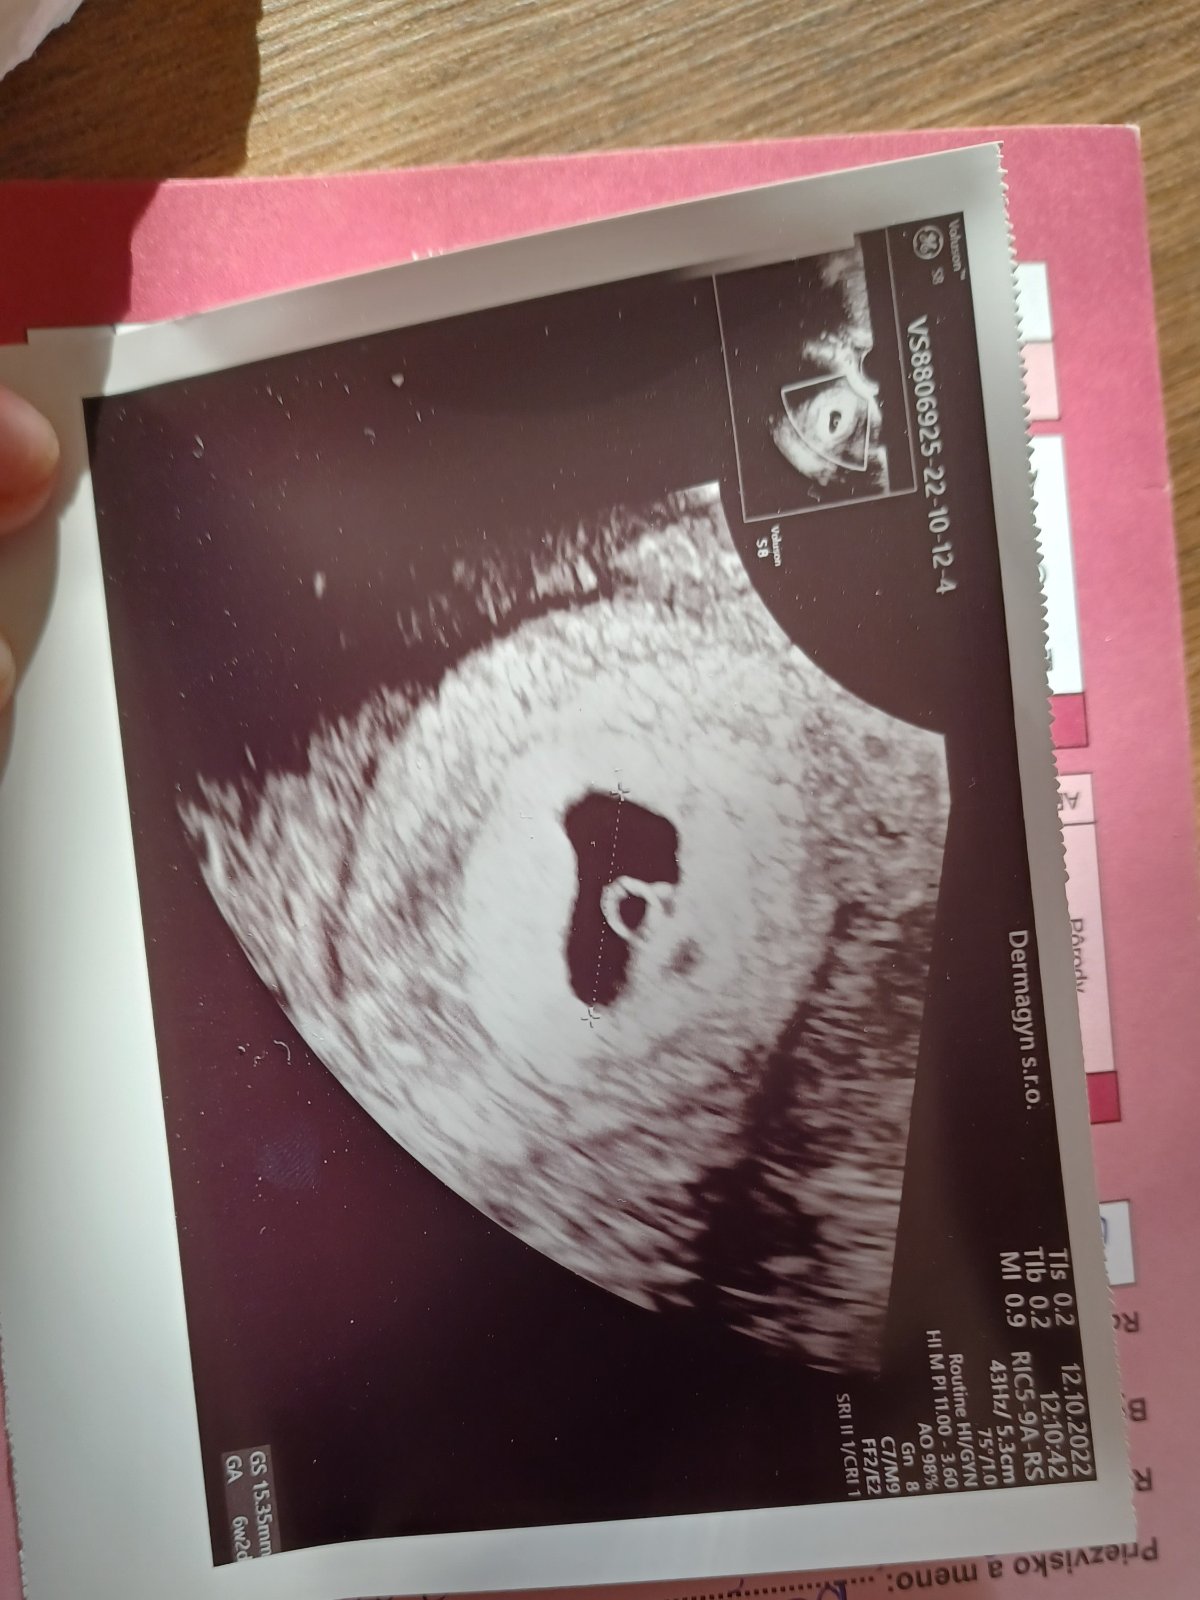

Ahojte potrebovala by som poradiť.Dnes som bola u svojej gynekologicky prvý krát.Mala by som byť 6+0 tt a znepokojilo ma to keď mi povedala že sa jej plod zdá malý a v tomto tt by už malo biť srdiečko.Mam sa začat báť?Vďaka za odpoveď.Mam za sebou potrat preto sa stresujem už teraz..Prikladám aj fotku zo sona

Ahojte.tak som dnes bola u dr.Dnes by som mala byť 7+1tt.srdiecko bolo,ale doktorka povedala,že slabšie s tým že je to normálne na začiatku tehotenstva.Len malinké má len 3,5mm čo sa mi zdá dosť málo.doktorka povedala,že má dobrú veľkosť,ale čo čítam na nete tak sa mi nezdá.tak uvidíme kontrola zase o týždeň.dakujem všetkým kočkám ktoré mi držali palce 😘